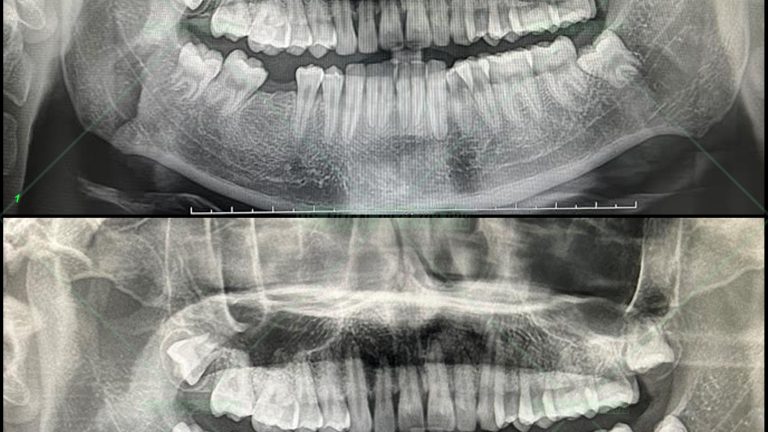

Ca này em họ vợ tôi, bắt đầu làm lúc mới học lớp 7 và vượt quãng đường 150km đều đặn hàng tháng từ Lạng Sơn xuống Hà Nội tôi chỉnh cho em, ca có nhổ 4 răng 4 trong 1 lần hẹn 1 cách khá dũng cảm. Kết quả không phụ sự kì vọng […]